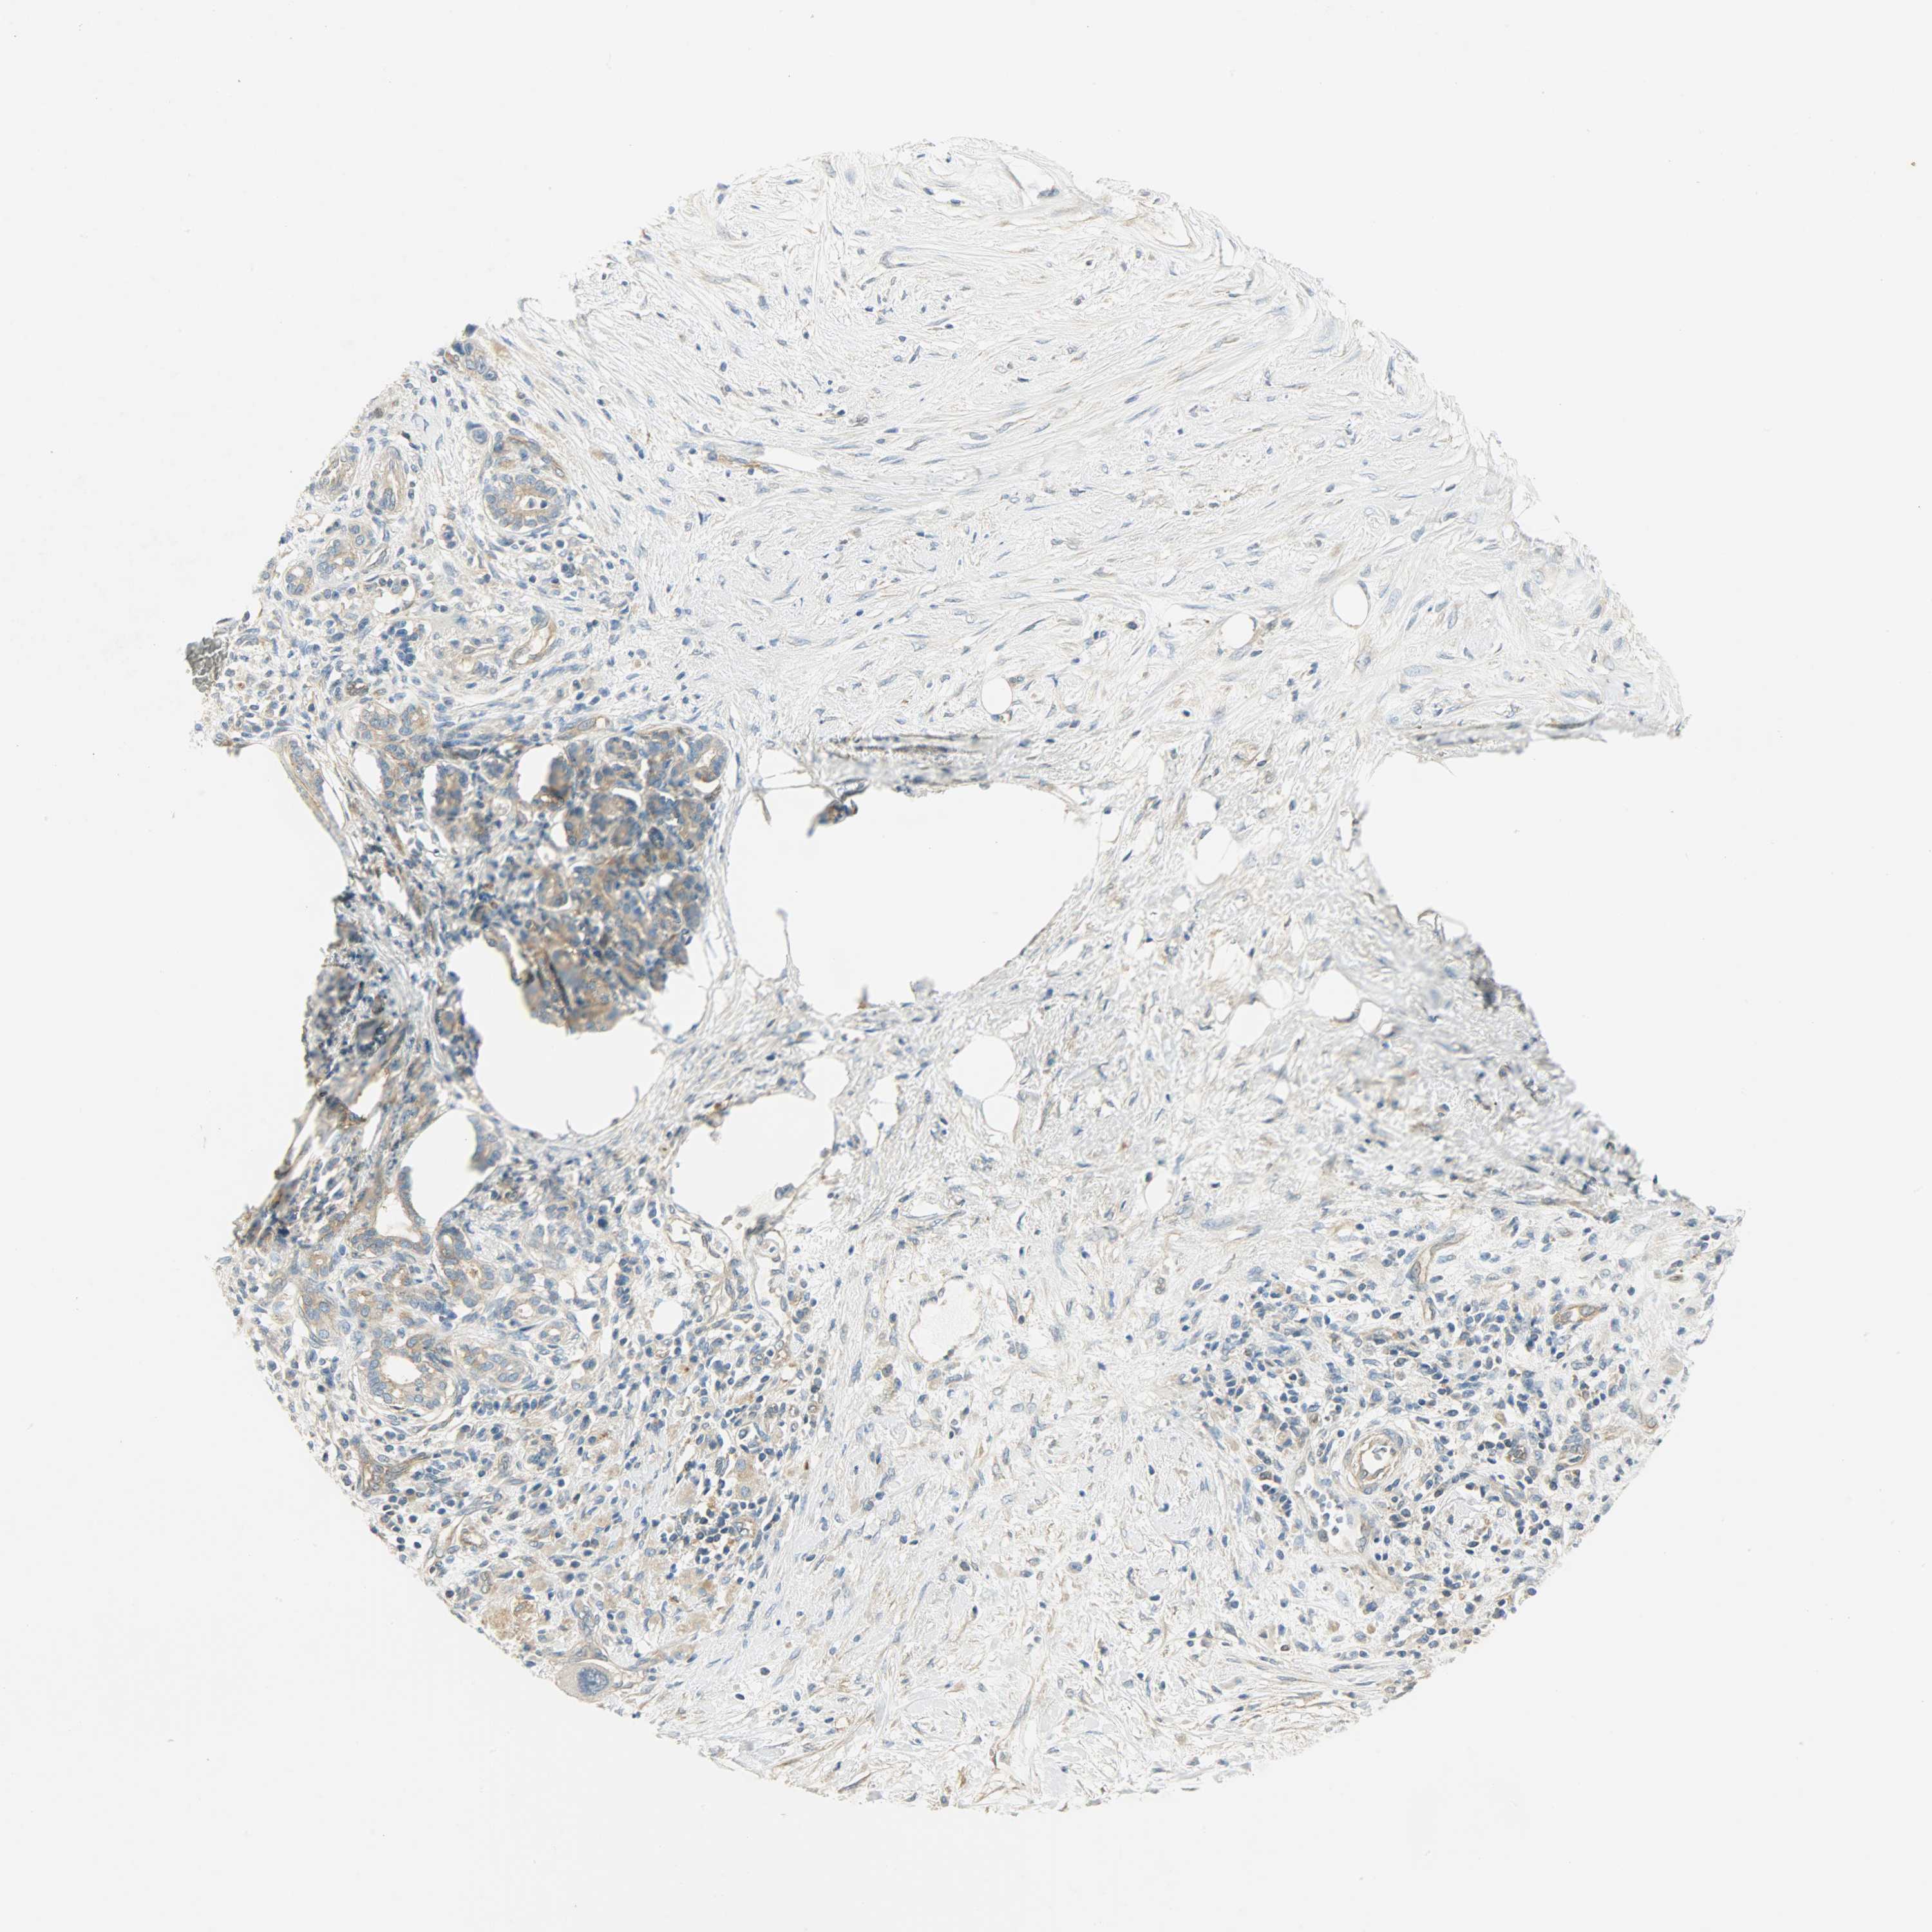

PANCREATIC CANCER - Protein expressioni

A mouse-over function shows sample information and annotation data. Click on an image to view it in a full screen mode. Samples can be filtered based on level of antibody staining by selecting one or several of the following categories: high, medium, low and not detected. The assay and annotation is described here.

Note that samples used for immunohistochemistry by the Human Protein Atlas do not correspond to samples in the TCGA dataset.

Antibody stainingi

Antibody staining in the annotated cell types in the current human tissue is reported as not detected, low, medium, or high, based on conventional immunohistochemistry profiling in selected tissues. This score is based on the combination of the staining intensity and fraction of stained cells.

Each image is clickable and will lead to virtual microscopy that enables deeper exploration of all samples and also displays staining intensity scores, fraction scores and subcellular localization as well as patient and tissue information for each sample.

Antibody HPA004926

Staining

High

Medium

Low

Not detected

Intensity

Strong

Moderate

Weak

Negative

Quantity

>75%

75%-25%

<25%

None

Location

Nuclear

Cytoplasmic/membranous

Cytoplasmic/membranous,nuclear

Adenocarcinoma, NOS

Adenocarcinoma, metastatic, NOS